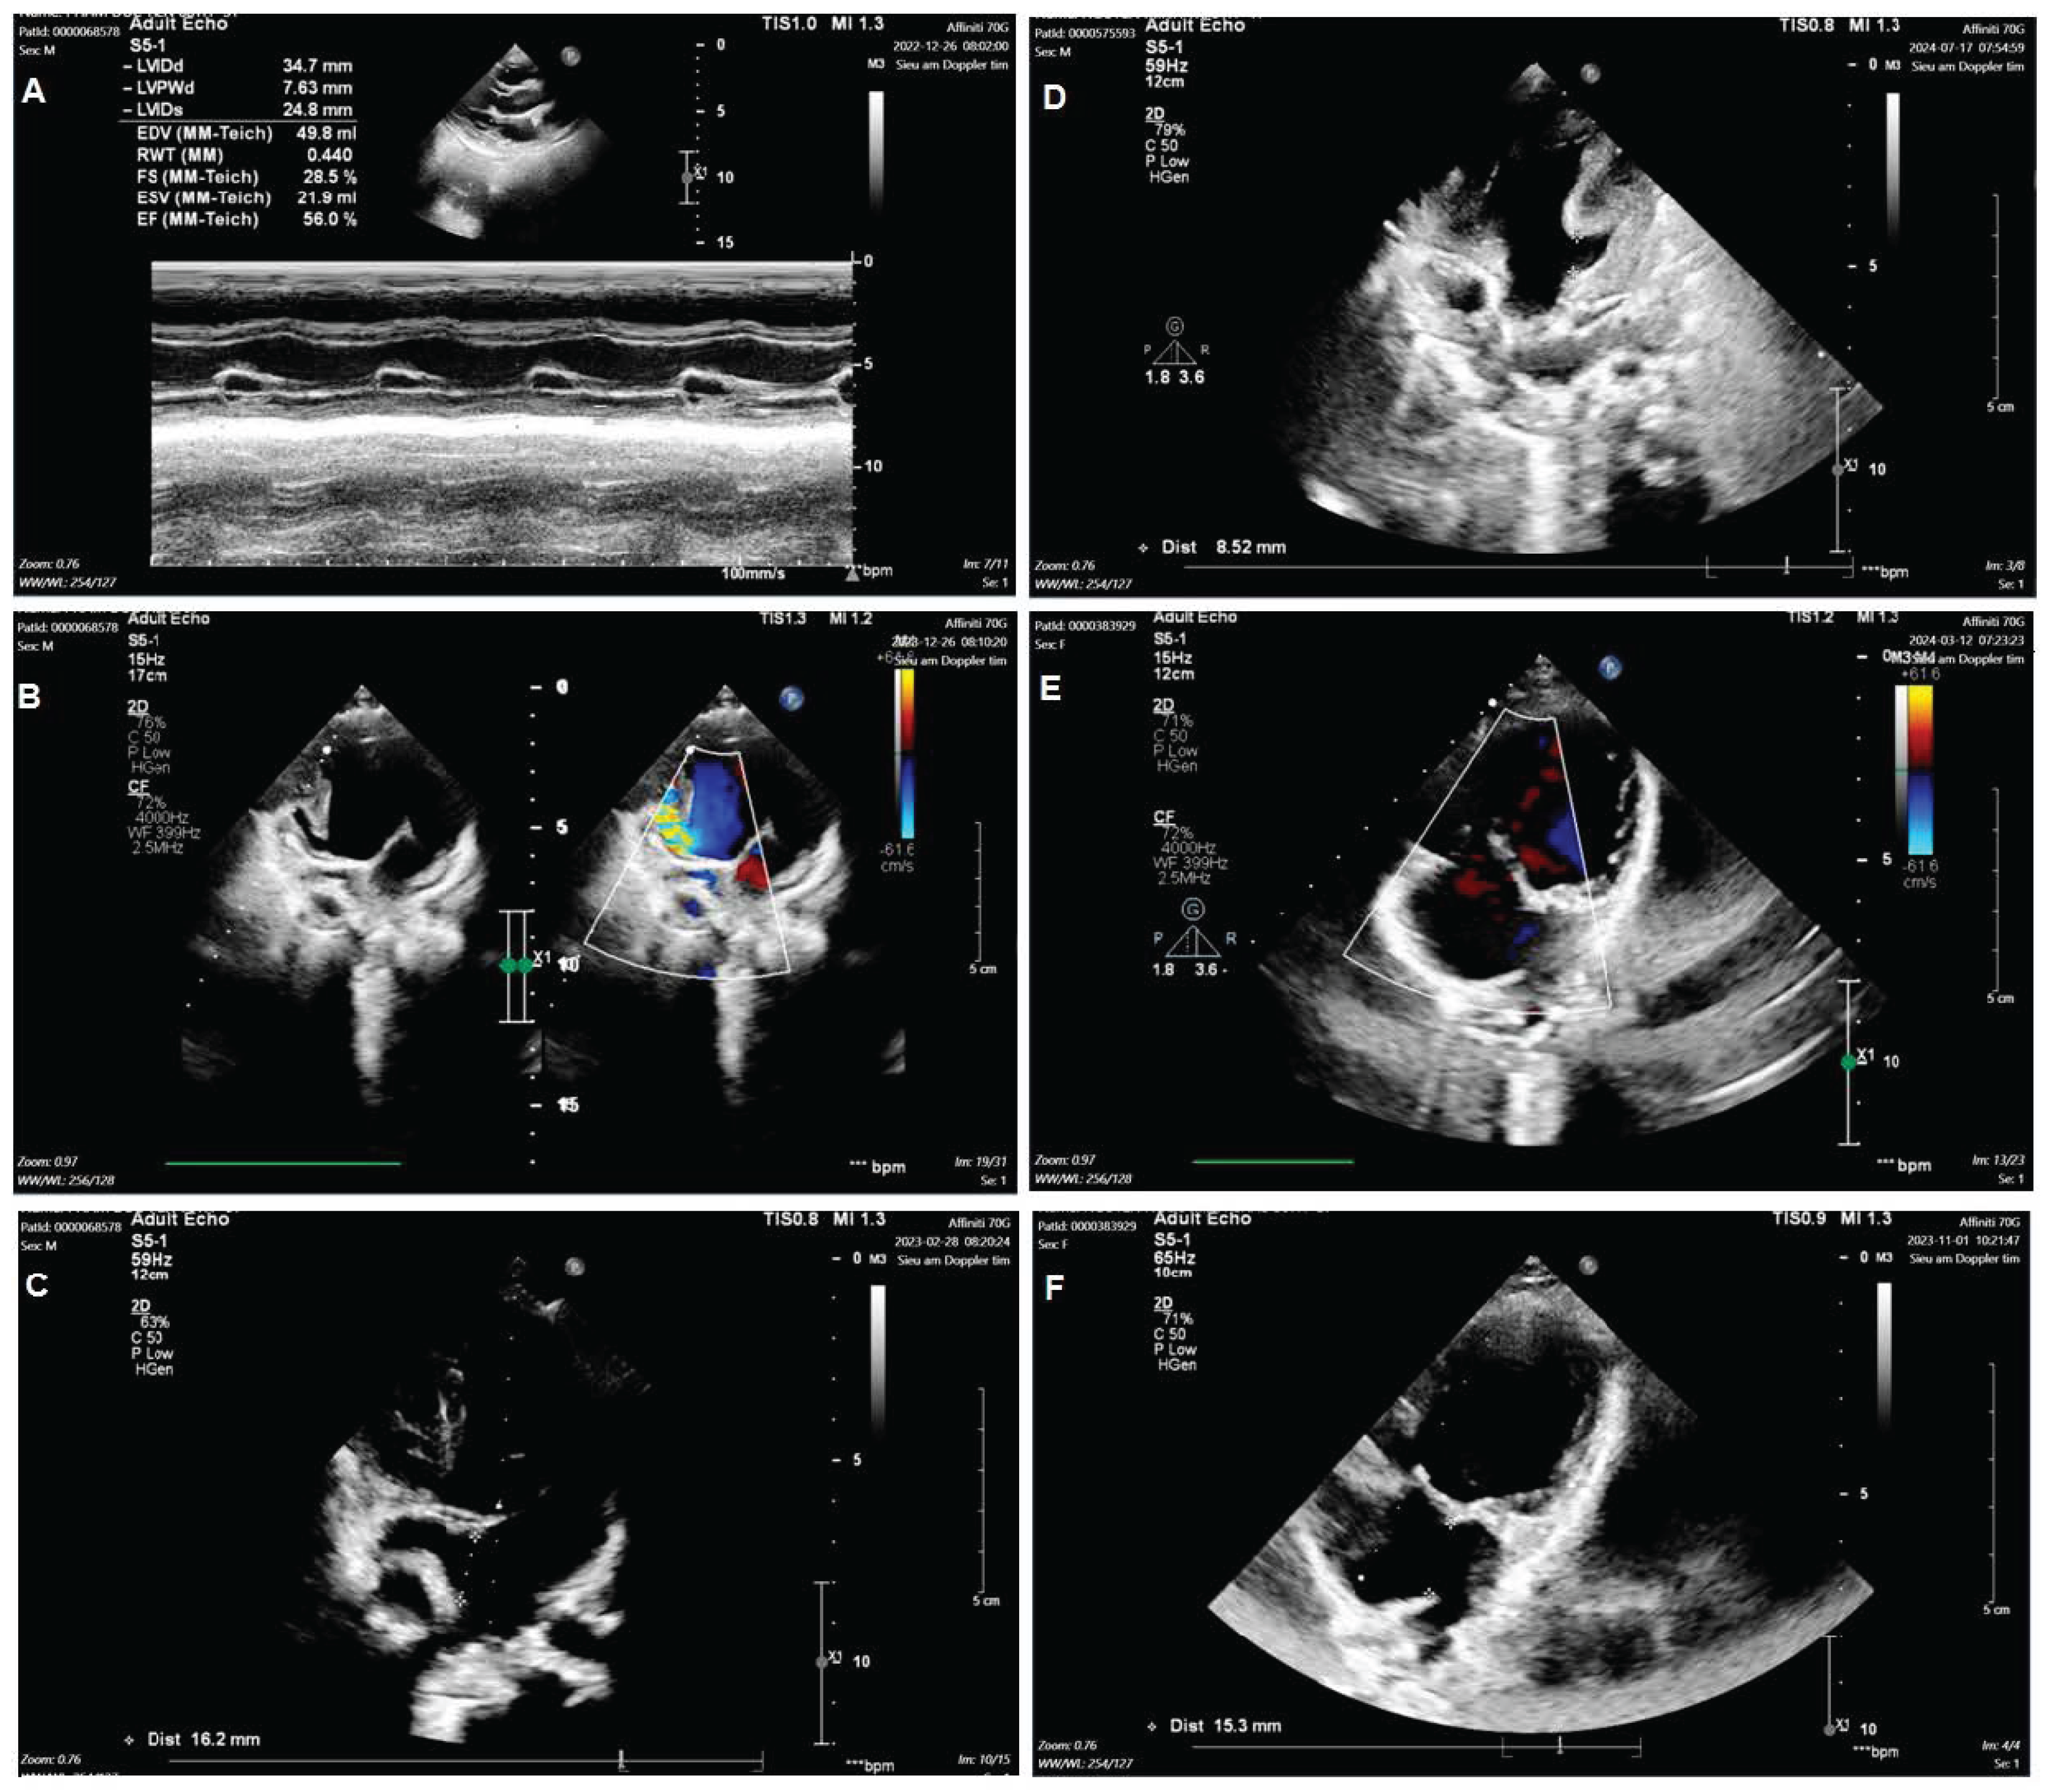

Group 1: Include nine TA patients with clinical features such as ASD, VSD, and PVS/PS (Figure 1A–C). The patients may have hypoplastic right ventricular, right ventricular outflow tract obstruction (RVOTO), DORV, TGA, and PDA. Group 2: Include three mitral valve atresia patients with clinical features such as hypoplastic left ventricular and DORV. The patients may have atrioventricular discordance, PDA, ASD, VSD, and TGA (Figure 1D–F). Group 3: Include twelve DORV patients with clinical features such as CAVSD and PVS/PS (Figure 2A–C). The patients may have a single atrium heart, a single ventricle heart, AAH, AS, ASD, VSD, TGA, and a total anomalous pulmonary venous connection (TAPVC). Group 4: Include five HLHS patients with clinical features such as AAH, AS, BAV, ASD, VSD, and PDA (Figure 2D–F).

Figure 2. Echocardiogram in the patient with double outlet right ventricle and in the patient with hypoplastic left heart. Including the image of assessment of Ventricular function (A); Double outlet right ventricle (B); Atrioventricular septal defects (C); Hypoplastic left heart (D); Pulmonary stenosis (E); Aortic stenosis (F).